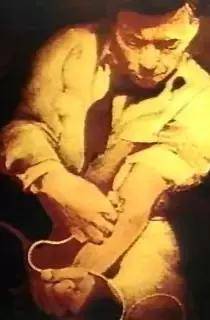

然而,趁著格爾達沒注意,福斯曼竟悄悄地背過身子,在自己的左臂打了局部麻醉藥藥物。

是的,福爾曼從來沒想過在格爾達身上做實驗,他只想通過格爾達獲得使用手術設備的權利罷了。

當麻藥起作用後,福斯曼就用手術刀切開了自己左臂肘部正中靜脈。

之後,他便拿起一根潤滑過的導尿管,緩慢地插入到自己靜脈大約30釐米處。

當他用無菌紗布蓋住了切口後,他這才解開了綁著格爾達手部的繩子。